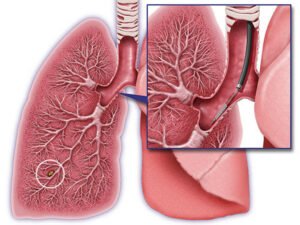

Lung Cancer

In lung cancer, PET scans detect malignant tumors, assess lymph node involvement, and identify distant metastases. They provide detailed images that help in staging the cancer, planning treatment, and evaluating the response to therapies.